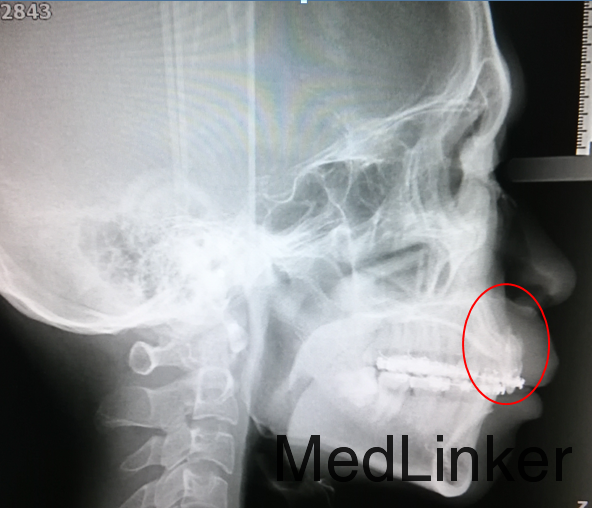

患者男,25岁, 外院转诊,上下牙齿粘有拖槽正在行正畸治疗,主诉牙齿拔牙间隙一直无法完全关闭,右上前牙近期冷热敏感

上前牙舌倾厉害,转矩完全丧失,上颌拔牙间隙少量约1-2mm。触摸A1牙根,根形明显,可见其根尖处有一突起,位于黏膜下,触诊较硬,疑为牙根尖穿出骨皮质所形成。侧位片确诊为牙根骨开窗,可见根尖已完全穿出骨皮质外。

治疗:暂停关间隙,尽快恢复患者上前牙唇倾度,于澳丝上排齐上牙列的同时弯制门形曲改善上前牙转矩,将穿出骨皮质外的A1牙根压入牙槽骨内,矫治后侧位片可见上前牙牙根已回到骨皮质内,直立在牙槽骨中,上前牙冷热敏感症状消失。矫治历时1年9个月。